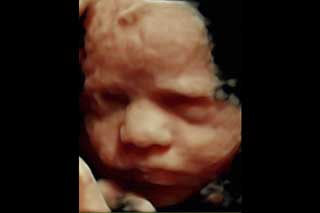

La evaluación 3D se basa en la obtención de imágenes 3D de algunas partes fetales, especialmente el rostro.

Ultrasonido en 3D

Reconstrucción digital de imágenes para formar una sola imagen en 3 dimensiones (3D), permitiendo así poder visualizar el rostro de su bebé.

La ecografía 3D es aquella que permite a usted ver la superficie corporal de su bebé, esto permite observar detalles como: labios, nariz, pómulos, frente, manos, entre otras.

Para lograr esto es necesario que se cumplan muchas condiciones como por ejemplo que el bebé no este mirando hacia atrás, que la placenta, el cordón o las extremidades no le tapen su rostro, así como que el líquido amniótico esté en cantidad suficiente.